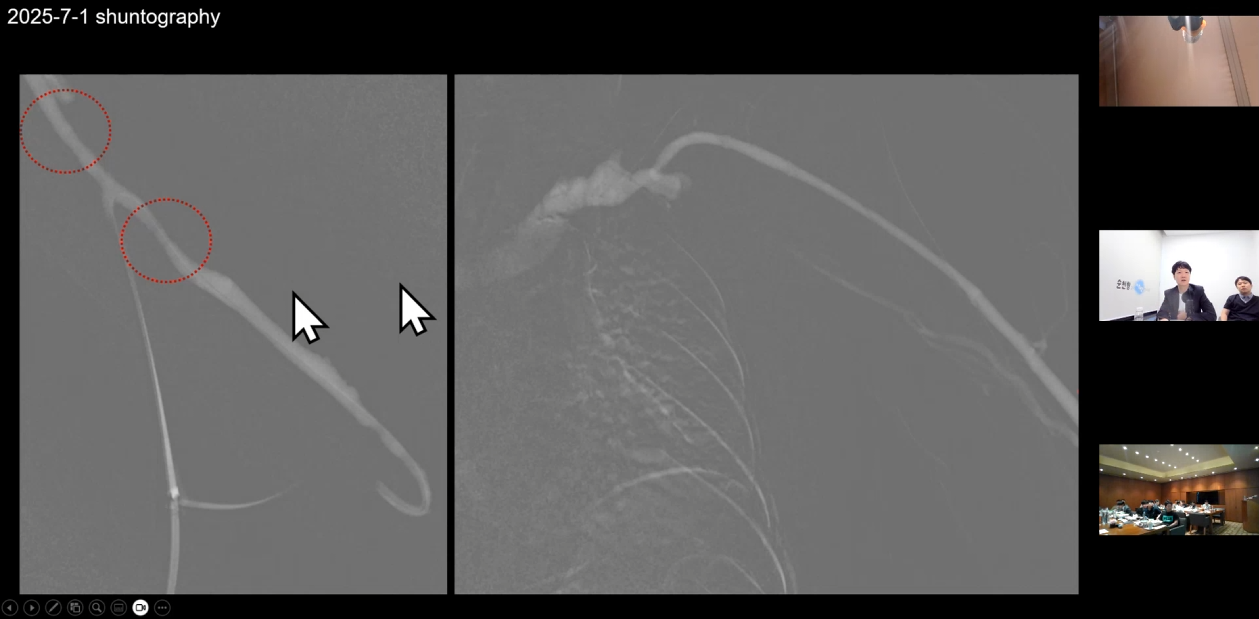

권요한 원장님은 'Can a DCB be a GAME changer?'라는 주제로

DCB에 대한 문헌 검토와

투석혈관 치료에서 DCB가 어떻게 사용되는지

시술 사례와 함께 치료 전략을 공유했습니다.